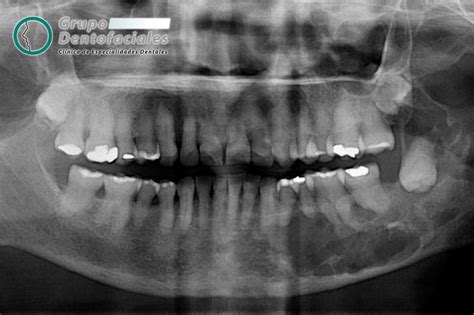

Radiografías y Diagnóstico Preciso

Antes de tomar cualquier decisión, es fundamental realizar radiografías panorámicas u ortopantomografías para evaluar la posición, inclinación y espacio disponible para la erupción de las muelas del juicio. Estudios radiográficos precisos proporcionarán información detallada que orientará al profesional en el tratamiento más adecuado para cada caso.